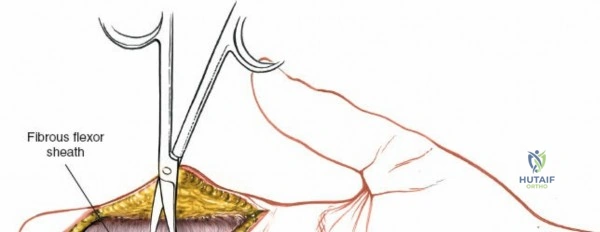

Fibrous Flexor Sheath Exposure

Once the subcutaneous tissue and neurovascular bundles are retracted, the fibrous flexor sheath is visible. This appears as a glistening white, tough structure enveloping the flexor tendons.

The sheath is incised longitudinally. The specific pulleys that need to be released depend on the pathology and zone of injury.

- A1 Pulley Release: For distal palmar or MCP joint access (e.g., trigger finger release, A1 pulley excision for tumor). The A1 pulley can be completely incised longitudinally from proximal to distal without significant risk of bowstringing, as the A2 pulley is the primary stabilizer at the proximal phalanx base.

- The A1, A3, and A5 pulleys, and the cruciate pulleys (C1, C2, C3), can be incised longitudinally or partially vented to expose the tendons and allow for repair.

- When accessing Zone II (no-man's land), the incision usually involves opening the A1, A3, and C1/C2/C3 pulleys, carefully preserving the A2 and A4 pulleys.